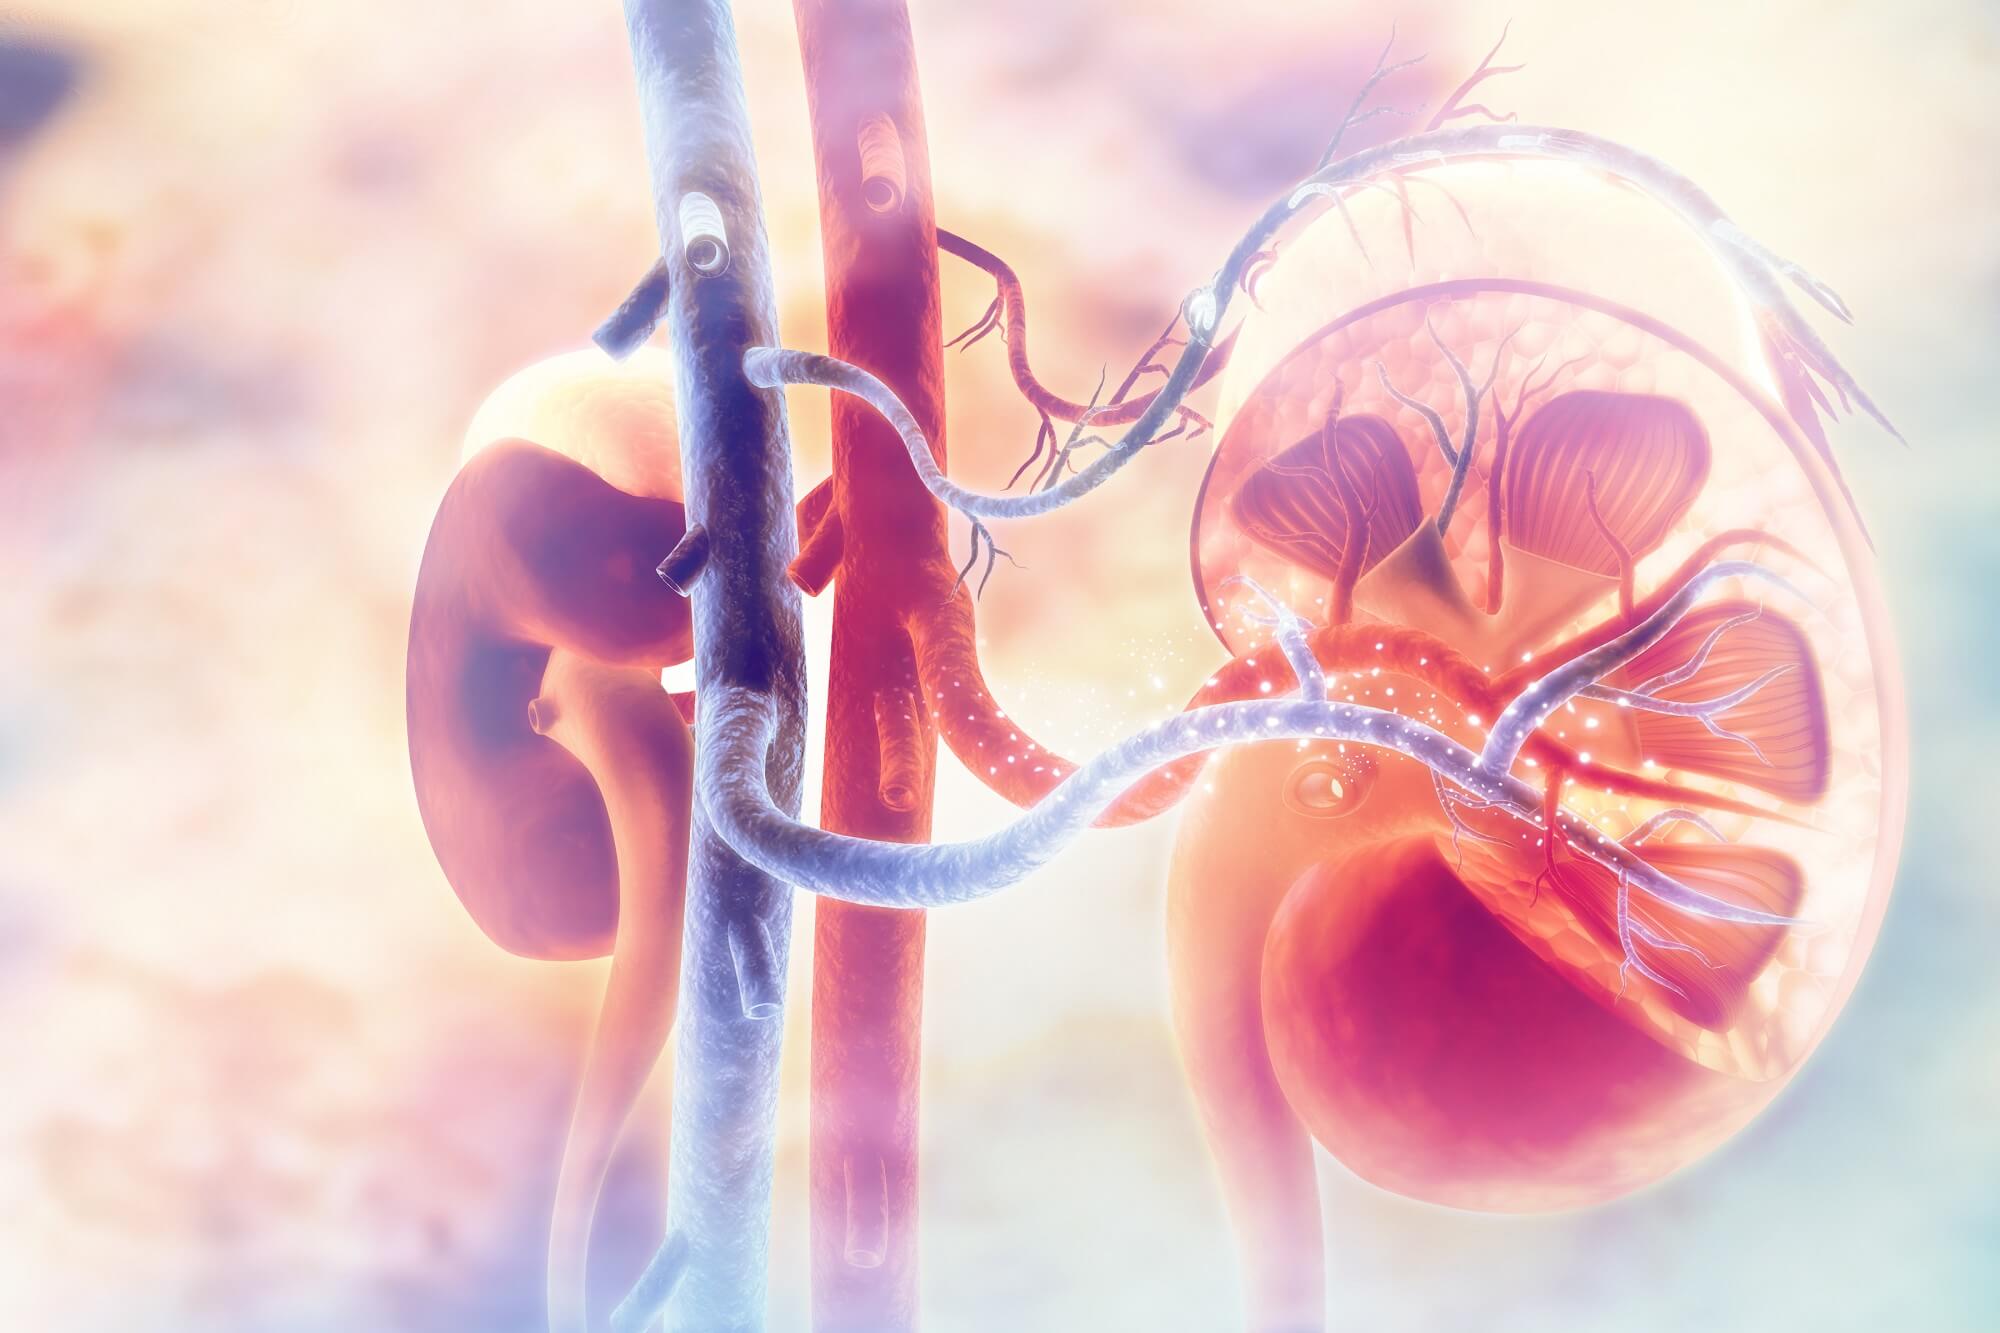

- Nephrology

- Urology